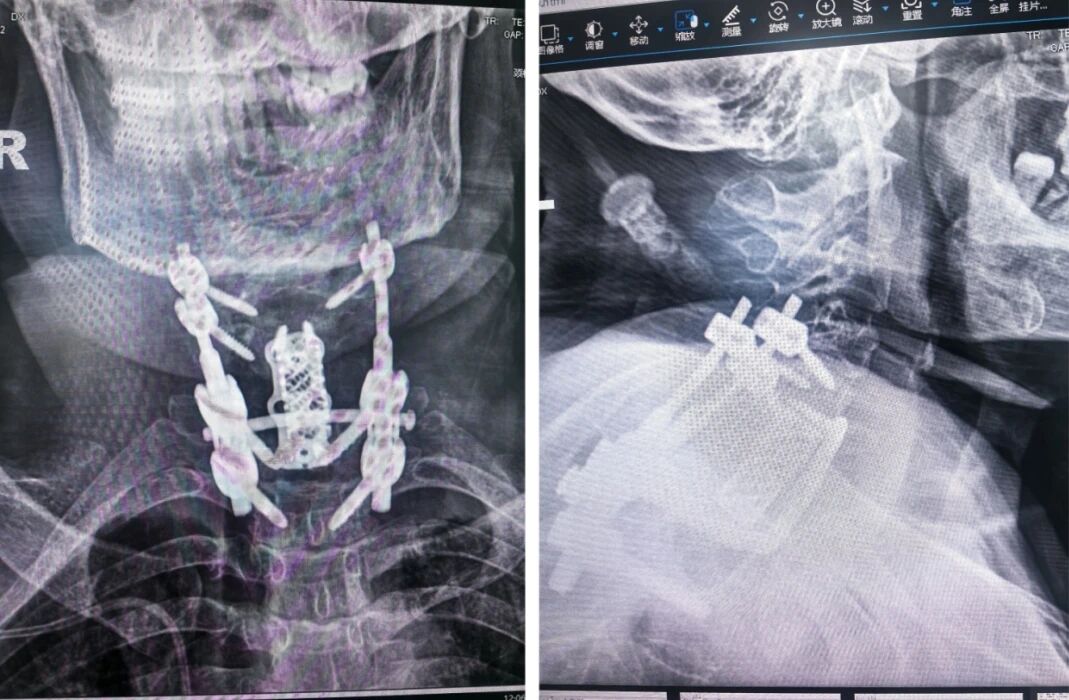

术后内固定影像